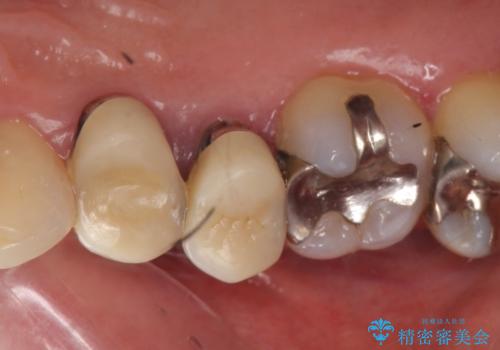

オールセラミッククラウン 歯根破折→抜歯→ブリッジ

- 右上の奥歯でものを咬むと痛むので診て欲しいといらっしゃった方の症例です。

診査の結果、歯根が破折しており保存不可能だったため抜歯し、ブリッジによる補綴を行いました。